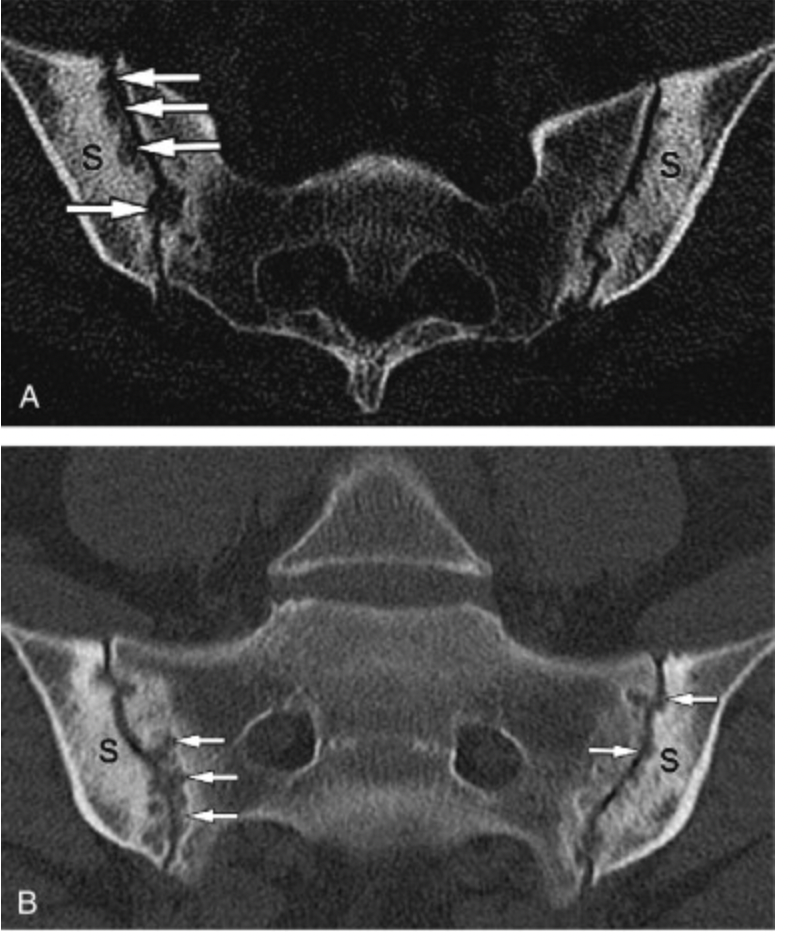

Sacrolititis

normal SI joint